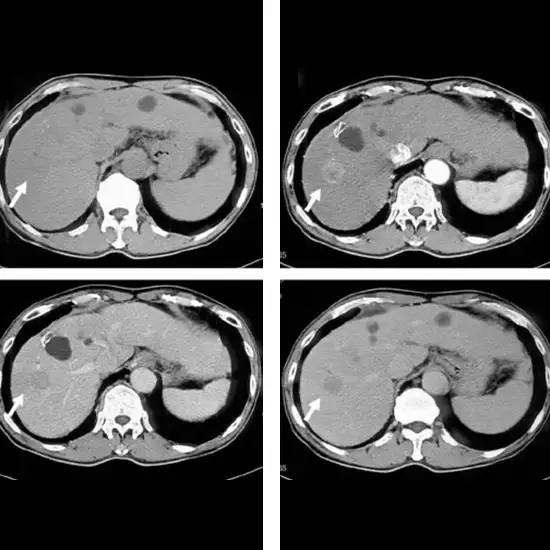

The Triple Phase CT Abdomen scan provides detailed images of the abdominal structure. In this scan, an X-ray beam is used to generate detailed images of the organs inside the abdomen, such as the GI Tract, Liver, Kidney, Pancreas, Spleen, and so on. A doctor may recommend this scan to diagnose the underlying cause of symptoms such as blood in the urine, abdominal pain, abdominal swelling, hernia, or kidney stone. It is also used to diagnose/detect cancers such as renal pelvis cancer, hepatocellular cancer, lymphoma, melanoma, ovaries, pancreas cancer, and Pheochromocytoma.